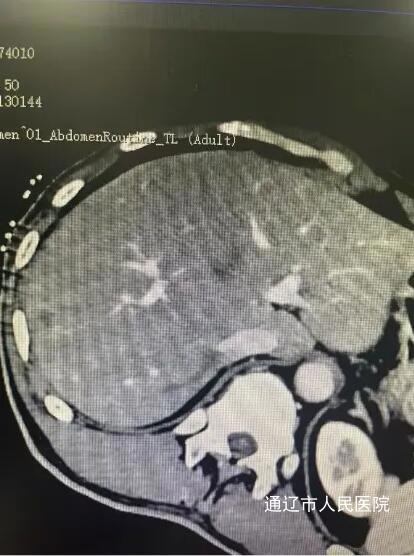

近日,我院肝胆胰外科成功实施了全市首例CT引导下肝肿瘤纳米刀消融术,标志着我院肝胆胰外科在肿瘤微创消融领域迈上新台阶,填补了本地区医疗技术空白。该患者男性,因腹胀于我院就诊,完善相关检查诊断结肠癌伴肠梗阻,肝占位性病变考虑转移瘤,讨论病情后决定一期行腹腔镜下根治性右半结肠切除术,术后复查腹部增强CT、增强肝脏MRI提示肝脏转移瘤有进展趋势,遂行CT引导下肝肿瘤纳米刀消融术。

手术过程中,患者行全身麻醉,在解放军总医院肖越勇教授指导下,我院肝胆胰外科主任医师郭雅明、手术麻醉科副主任医师高飞、CT室医护团队在CT引导下确认病灶位置并进针,确保电极区域完全包裹肿瘤后开始消融。消融过程中电流上升反馈良好,术后即刻增强CT显示消融范围覆盖病灶,周围血管、胆道结构完好无损伤,出现明显气体影,消融效果良好。消融完成后,退出穿刺针,手术顺利结束,术中麻醉效果满意,生命体征平稳,麻醉恢复后无腹痛腹胀,恶心呕吐等不适。术后给予对症支持治疗,患者恢复良好。和传统的消融治疗方式不同,纳米刀消融技术是通过脉冲电场导致细胞不可逆电穿孔,从而实现肿瘤组织杀伤,是一种非热选择性物理消融技术,可在实现消融肿瘤的同时,保留肿瘤周围的重要管道结构(血管、胆管和神经)完整性,并且无热沉效应,消融肿瘤细胞,适用于消融治疗靠近肝门、胆囊、膈肌和结肠等肝脏特殊部位的肿瘤有着独特的优势。纳米刀消融手术为现阶段先进、安全的肿瘤消融技术,它为无法使用传统手术方式的特殊部位癌症患者提供了新的治疗方式,还具有能够选择性消融,时间短、创口小等优点,一定程度上能够改善生活质量,延长生存时间,纳米刀消融对不能手术的肝癌、肺癌特别是胰腺癌具备较大的技术优势。此次全市首例纳米刀消融术的开展,标志我院微创介入技术取得重大突破,也为疑难肿瘤患者提供了更为先进技术的诊疗手段。